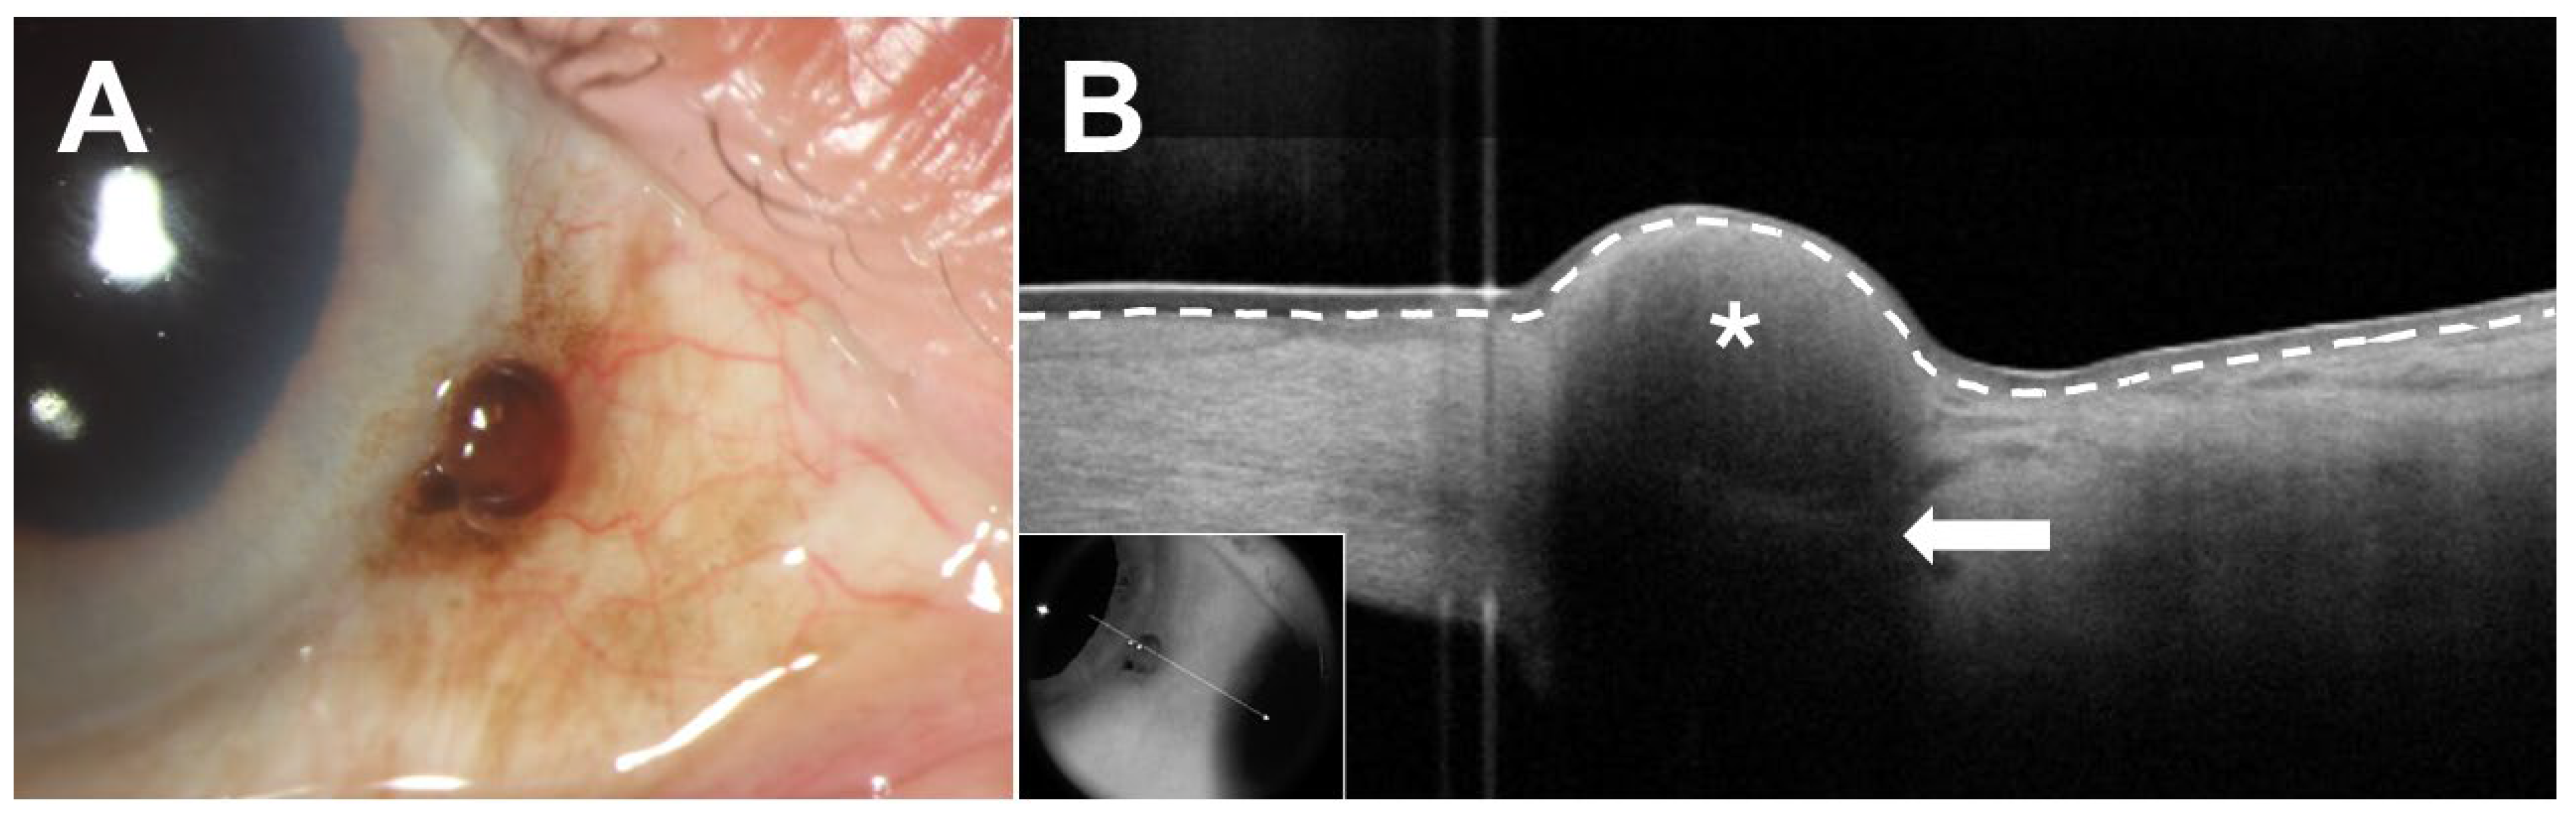

4.2. Current Applications of UBM

- Meel, R.; Dhiman, R.; Sen, S.; Kashyap, S.; Tandon, R.; Vanathi, M. Ocular Surface Squamous Neoplasia with Intraocular Extension: Clinical and Ultrasound Biomicroscopic Findings. Ocul. Oncol. Pathol. 2019, 5, 122–127. [Google Scholar] [CrossRef]

- Kaliki, S.; Jajapuram, S.D.; Maniar, A.; Taneja, S.; Mishra, D.K. Ocular surface squamous neoplasia with intraocular tumour extension: A study of 23 patients. Eye 2020, 34, 319–326. [Google Scholar] [CrossRef]